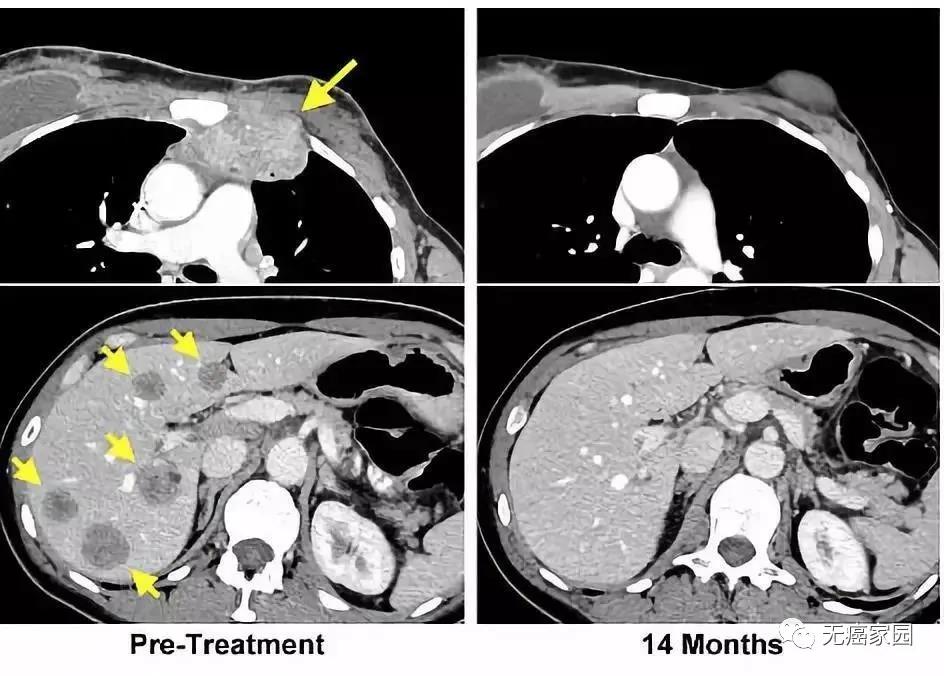

TILs疗法让生存期仅剩3个月的乳腺癌患者重获新生

Dr. Rosenberg将提取出的肿瘤细胞分成24份,然后观察肿瘤浸润性淋巴细胞(TIL)是否攻击这些癌细胞。结果发现,24份肿瘤细胞中有4份发生了免疫细胞攻击癌细胞的现象。随后,将这四份肿瘤中应用的TIL细胞提取出来,进行扩增,形成数以亿计的能够攻击癌细胞的T细胞,用于回输到Ms. Perkins体内。

一周过后,Judy Perkins感觉自己的身体起了明显的变化。比如她长在胸部的肿瘤,感觉逐渐缩小。又过了一两周,胸腔内的肿瘤荡然无存。

Ms. Perkins被治愈这一事实给癌症患者及癌症疗法研究者带去了极大的鼓舞。虽然她只是一个个例。但是她体内转移性乳腺癌细胞已经检测不出这一事实,是一非常重要的结果。